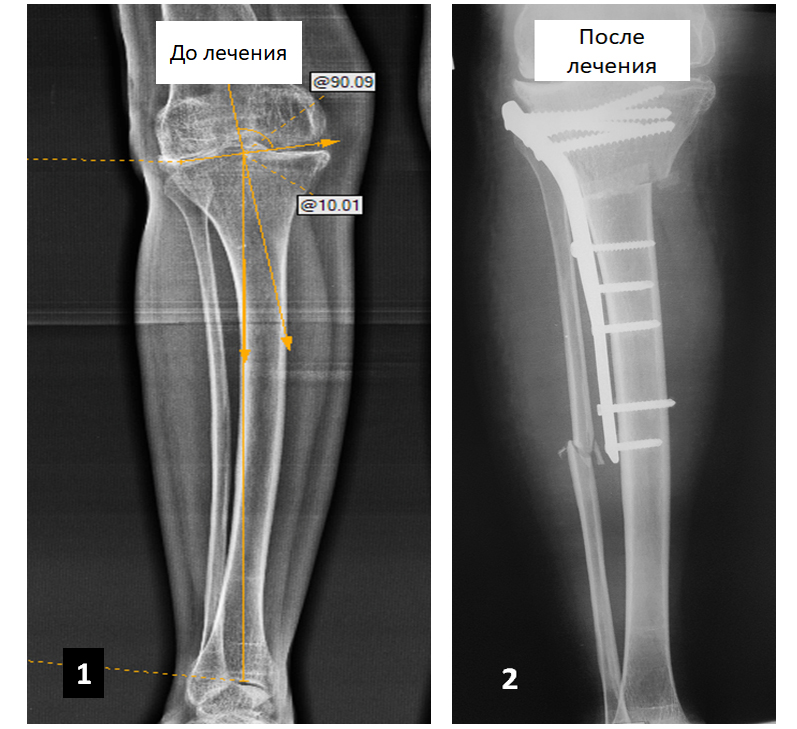

У пациентки 43 лет на фоне дисплазии тазобедренного сустава развилась выраженная установочная вальгусная деформация левой голени (см. фото 1), которая сопровождалась значительными болями в области коленного и тазобедренного суставов, которые возникали сразу же при начале ходьбы. В специализированном медучреждении пациентке было предложено выполнить протезирование тазобедренного и коленного суставов, от которых она отказалась. Нами были одномоментно выполнены восстановительные оперативные вмешательства в области голени (см. фото 2) и тазобедренного сустава. После реабилитационного лечения пациентка полноценно пользуется левой ногой и может длительное время ходить пешком без каких-либо болей в суставах.